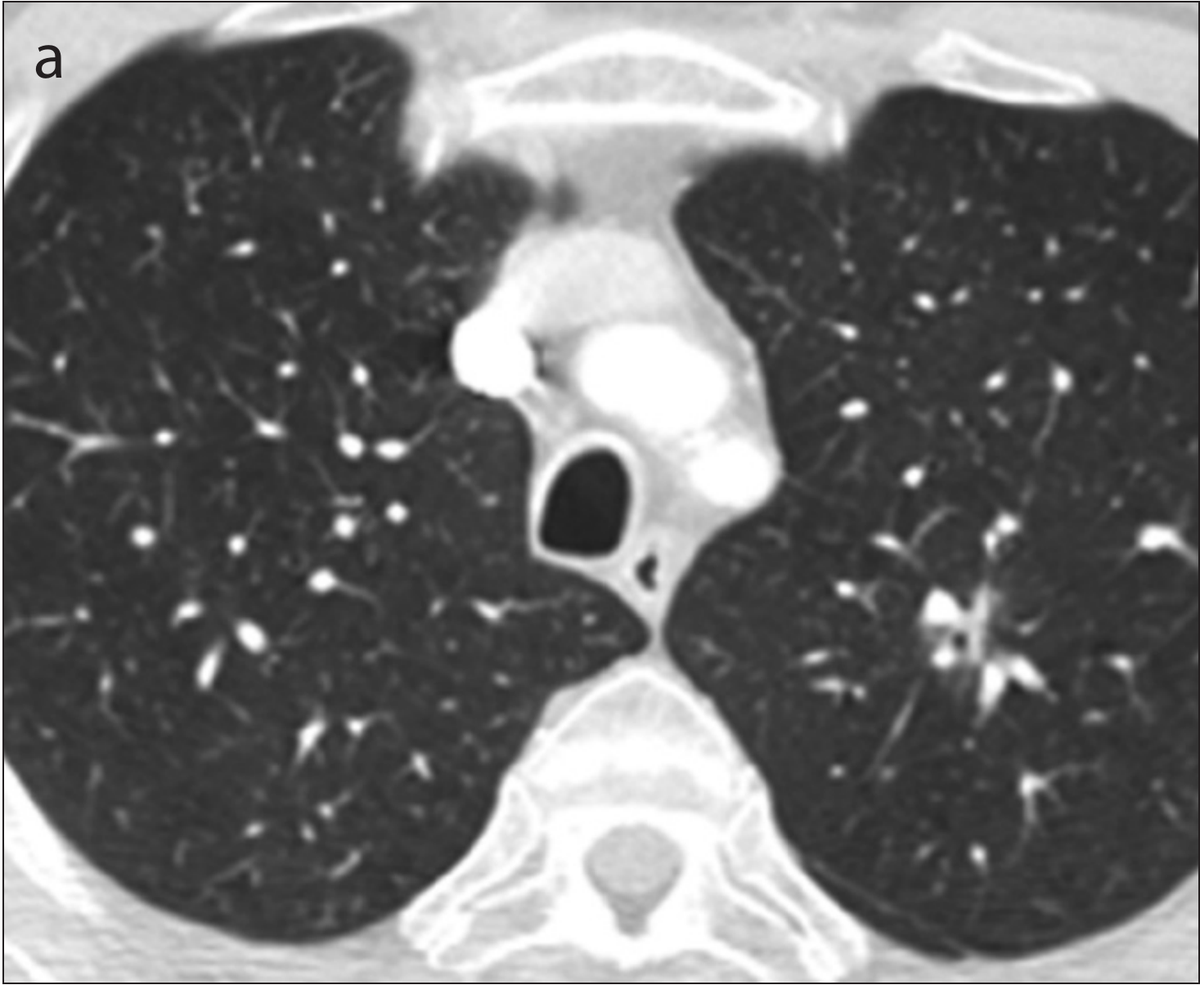

Another 2019 study (Ardila et al), a collaboration between Google's Deep Mind and Northwestern University, reported promising results for better detecting small tumors in CT. The researchers created a three-dimensional AI model that was able to take into account regions of concern within the lung. Making use of both current scans and those from before receiving a lung cancer diagnosis, the model showed good accuracy (94%) in detecting cancerous nodules; outperforming six radiologist reviewers while also reducing the number of false positives and false negatives.

The model's ability to analyze a volume, rather than "merely" a sequence of two-dimensional slices appears to have provided a benefit. The context of the additional pixels allowed the model to inspect patterns in blood vessels and other connective tissue not part of the tumor. This caused the model to highlight contributing factors not directly part of the growth, but capable of providing insight into its development and better predictive accuracy.